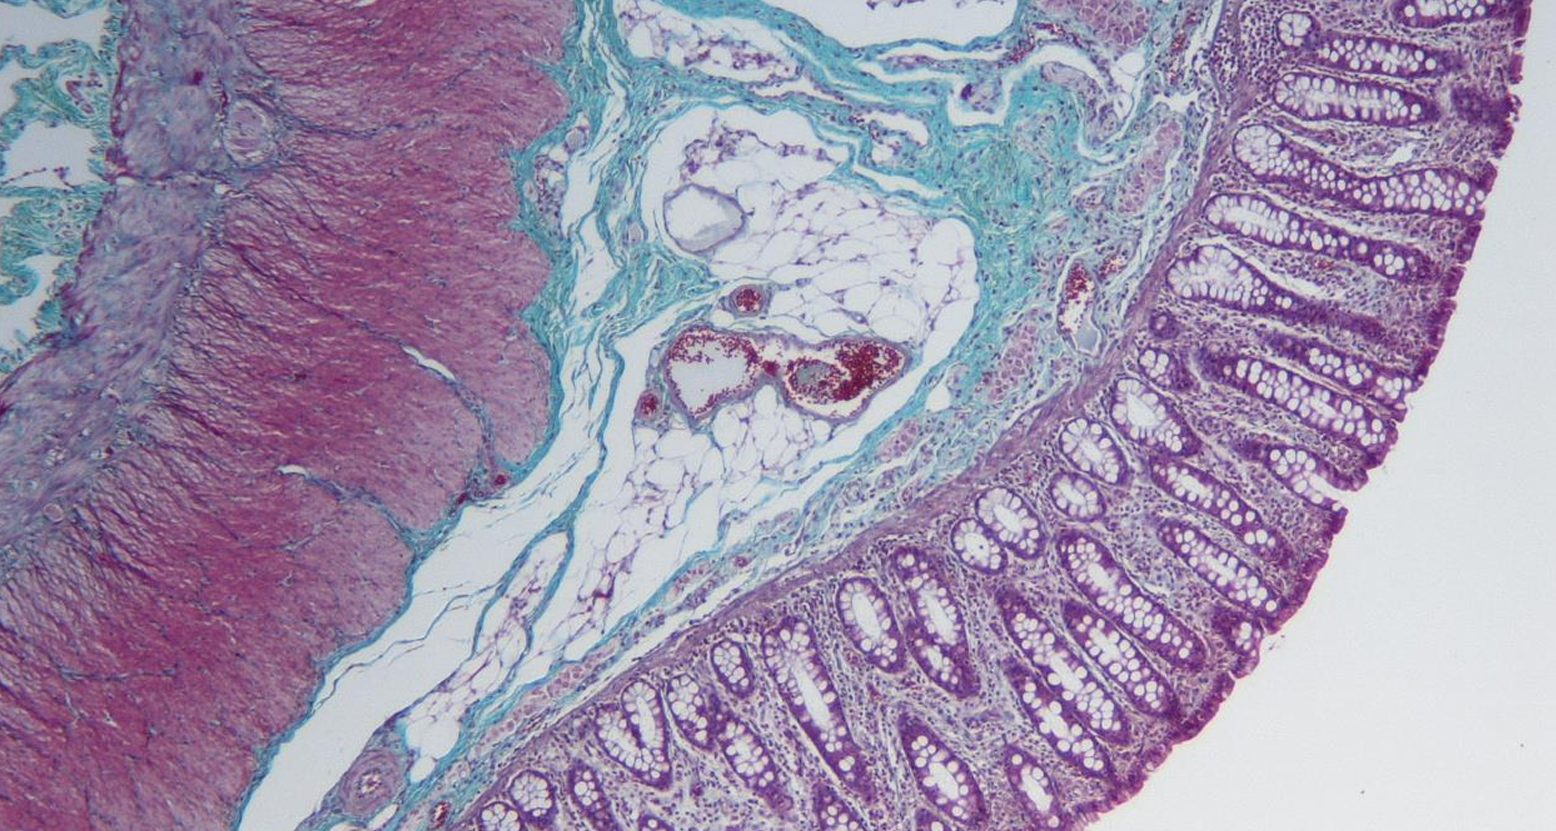

intestino grueso es la parte final del sistema digestivo, encargada de absorber agua y electrolitos, además de formar y eliminar las heces.

intestino grueso